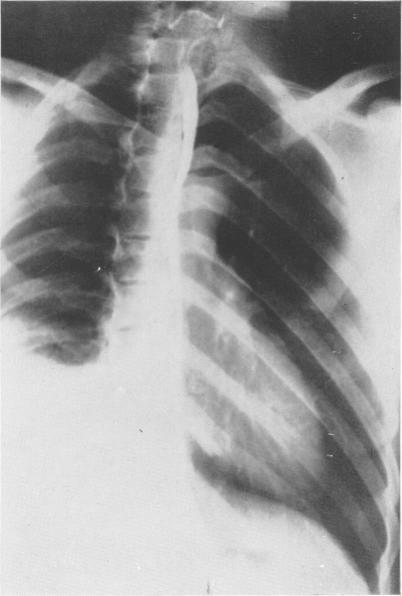

https://cdn.ncbi.nlm.nih.gov/pmc/blobs/71c1/1477067/ab4cf986c8e7/annsurg00452-0094-a.jpg